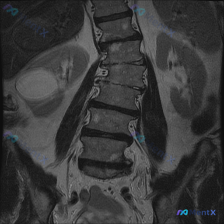

整理到一份影像读片资料,有点意思,放出来讨论下。 先看核心发现: - 腰椎MRI T2冠状位:明显向左侧凸畸形;椎体边缘骨赘形成,部分椎间隙非对称性变窄;凹侧椎间孔区域相对狭窄。 - 额外发现:右侧(图像左侧)肾脏内见边界尚清的明显高信号影。 影像科初步分析里提了“退行性脊柱侧弯”的依据很足,但同时...